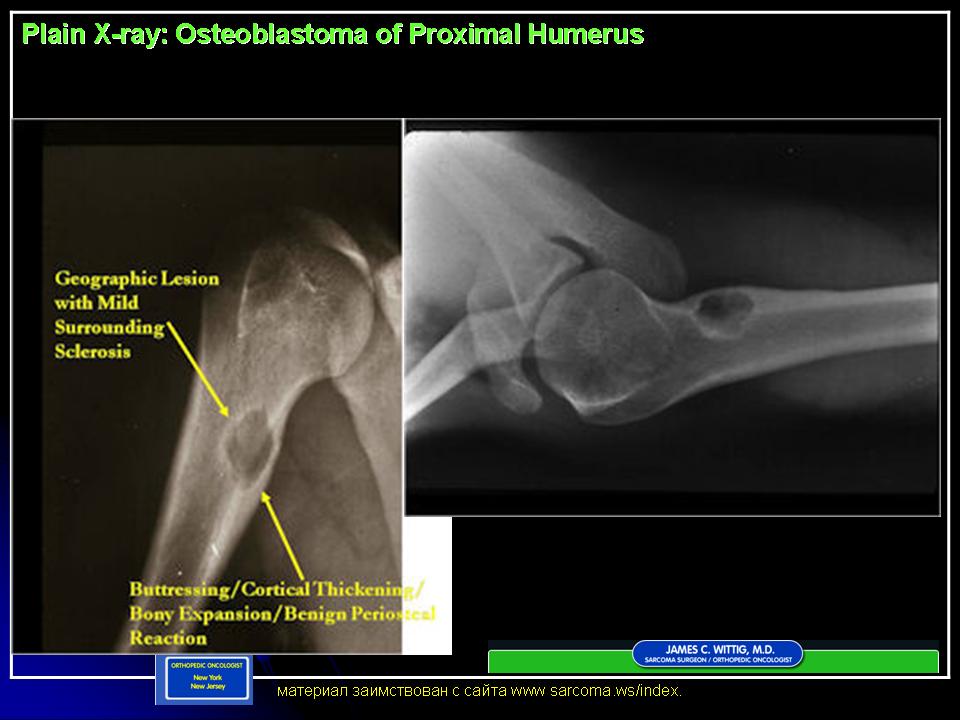

Остеобластома

Рентгенологическая картина остеобластомы представляет литический или смешанный, четко очерченный округлый или овальный дефект целостности кости с периостальной реакцией и зоной реактивного костеобразования.